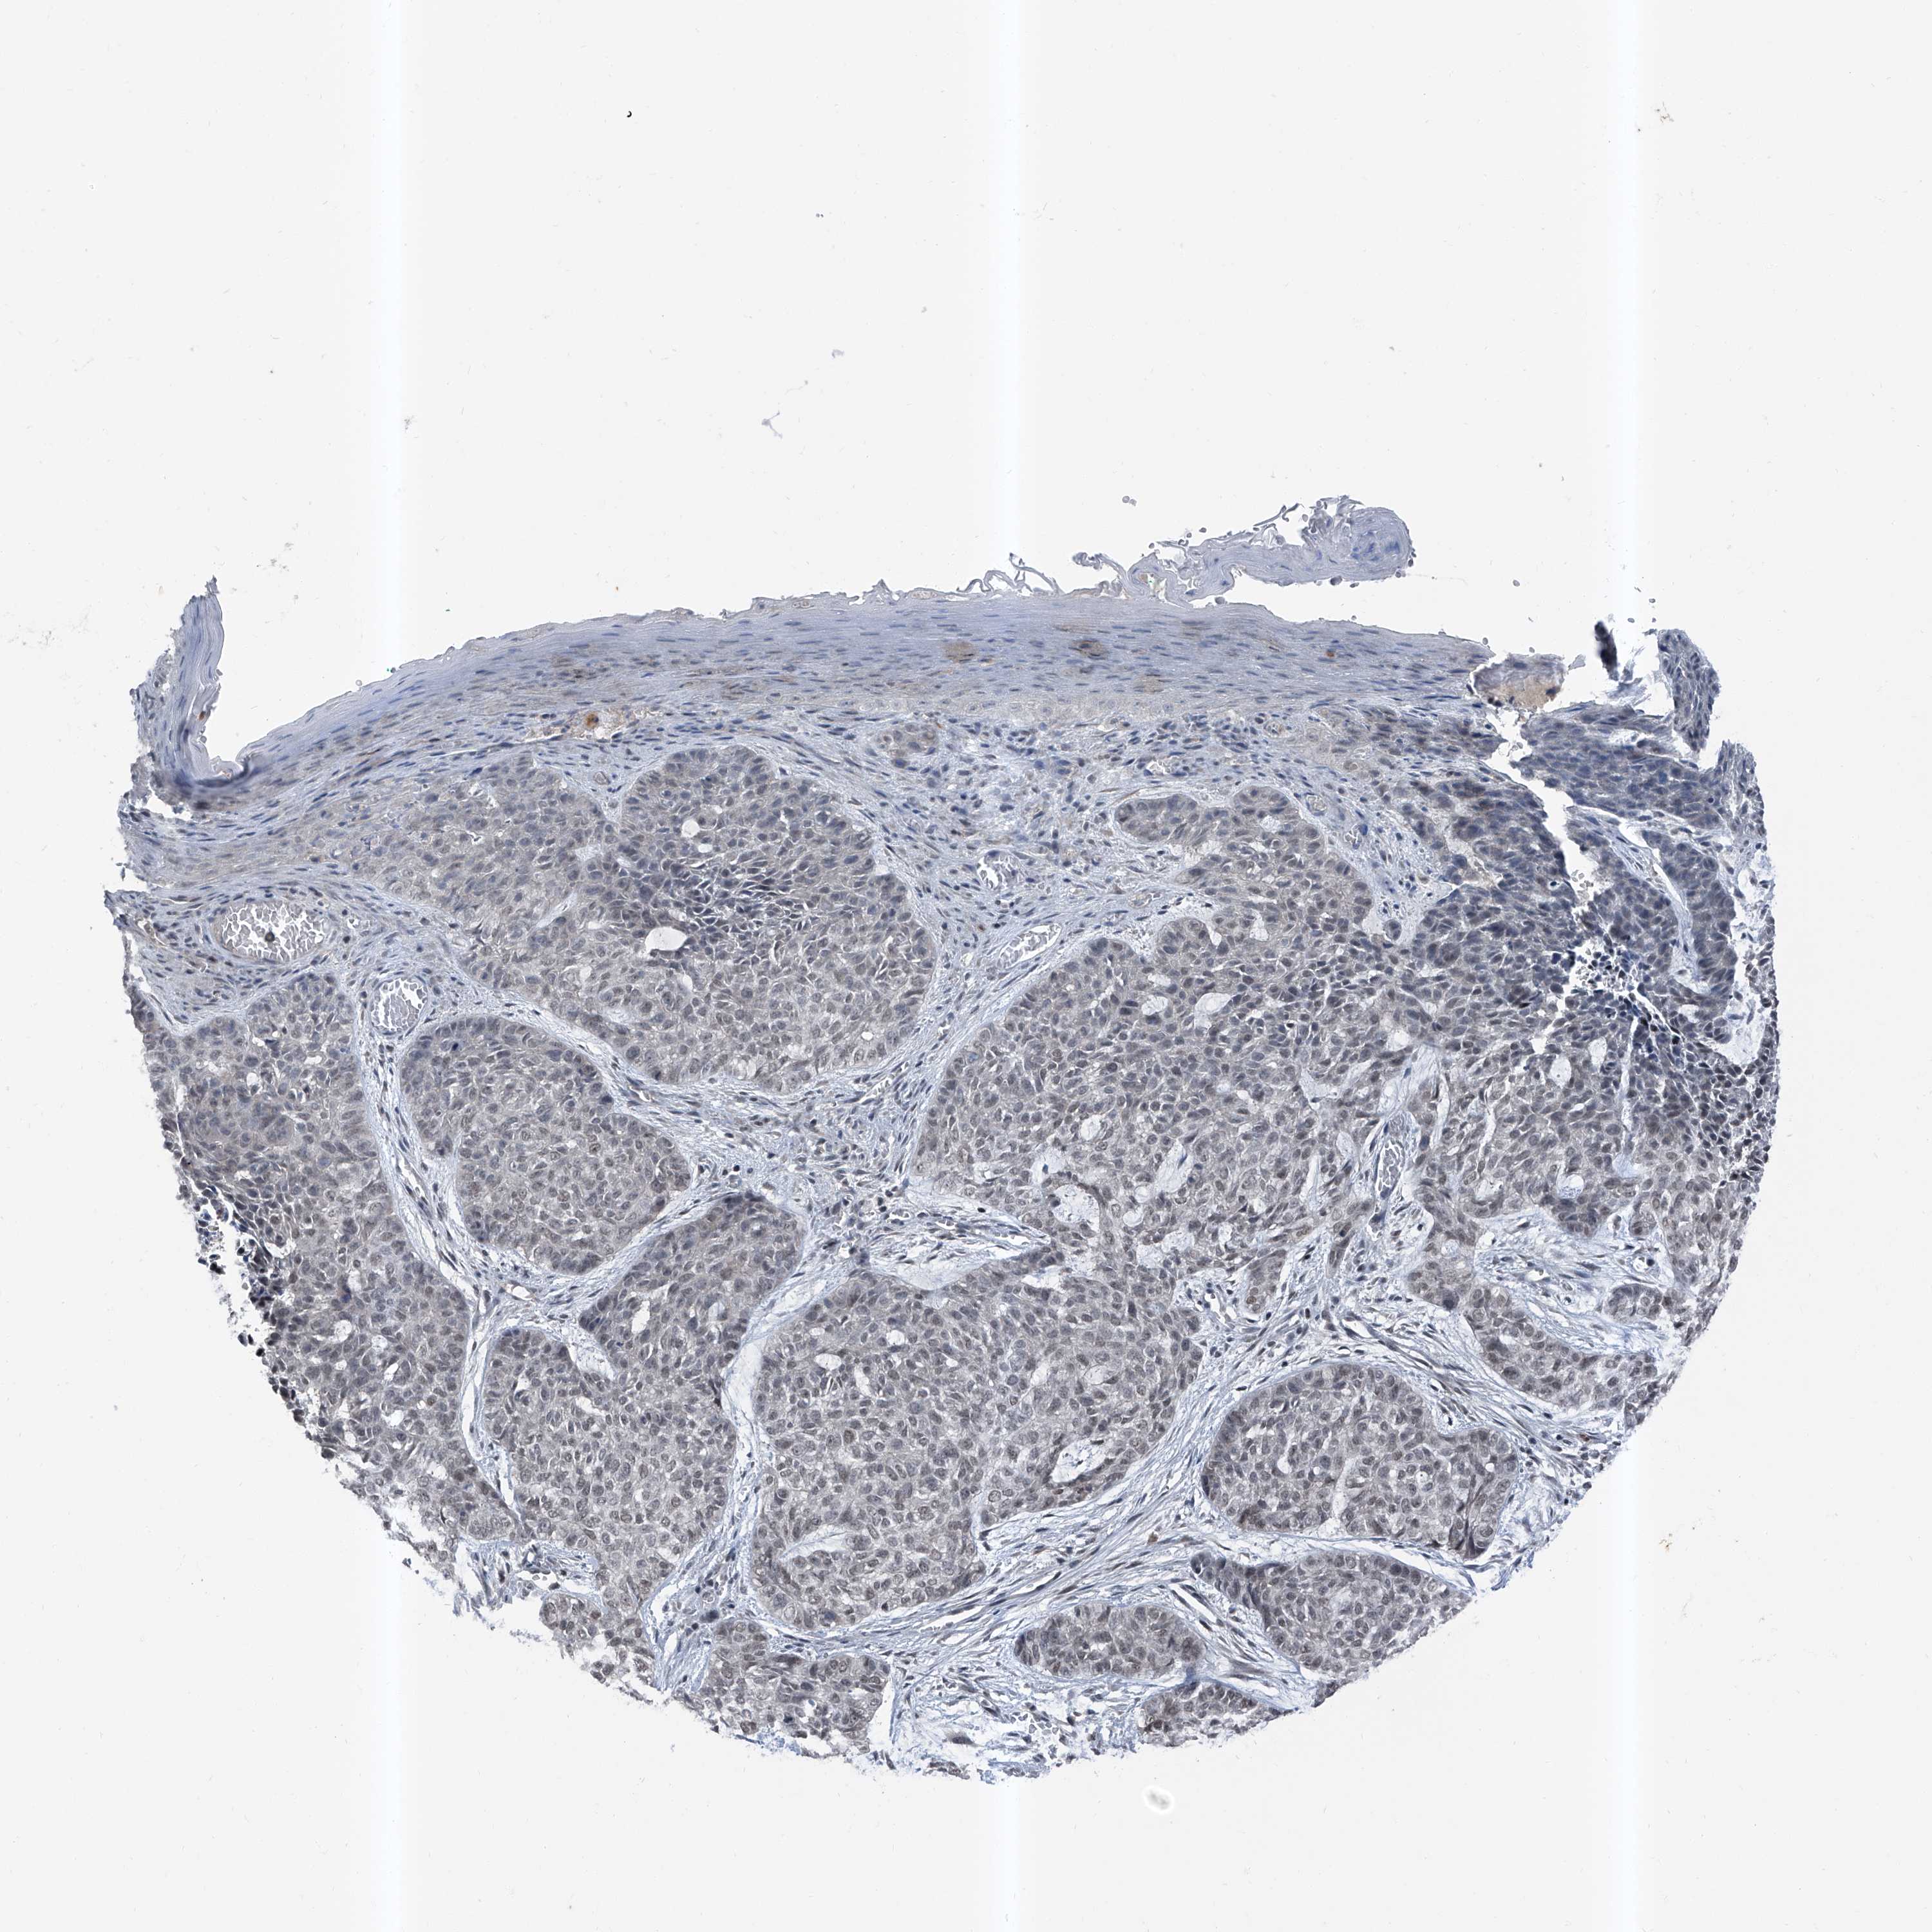

Basal cell and squamous cell cancer

SKIN CANCER - Protein expressioni

A mouse-over function shows sample information and annotation data. Click on an image to view it in a full screen mode. Samples can be filtered based on level of antibody staining by selecting one or several of the following categories: high, medium, low and not detected. The assay and annotation is described here.

Each image is clickable and will lead to virtual microscopy that enables deeper exploration of all samples and also displays staining intensity scores, fraction scores and subcellular localization as well as patient and tissue information for each sample.

Antibody HPA030472

Antibody HPA036584

Basal cell carcinoma

Squamous cell carcinoma, NOS

Squamous cell carcinoma, metastatic, NOS